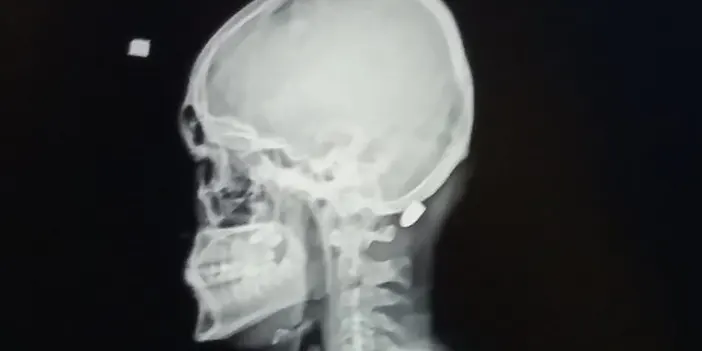

Kentte yetkililerin tüm uyarılarına rağmen yorgun mermi vakalarının arkası kesilmiyor. Yorgun mermi vakalarında kimileri hayatını kaybediyor, kimileri yaralanıyor, kimileri de sakat kalma tehlikesi ile karşı karşıya kalıyor. Trabzon’un Ortahisar ilçesinde 9 Nisan 2016 tarihinde M.M. (22) isimli inşaat işçisi işe giderken otobüs durağı yakınında nereden ve kim tarafından atıldığı belli olmayan ve "Yorgun mermi" diye tabir edilen merminin hedefi oldu. Merminin başına isabet etmesi sonucu M.M. ağır yaralandı.